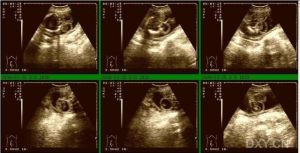

5.在修復顱後部腦膨出後,顱腦超聲是追蹤腦室大小、有無腦積水形成的有效手段。一旦有腦積水形成則需行腦脊液分流手術。

腦膨出預防:隨著胎兒超聲檢查及母血中α-胎蛋白檢測的常規套用,腦膨出在宮內即可獲得診斷,這對決定是否終止妊娠有重要作用。胎兒超聲檢查可以發現大的腦膨出,也容易探測囊內有無實質性組織。腦積水在產前超聲檢查中不常被發現。

事實上,腦積水鮮有在出生時就存在的,通常在顱後部腦膨出修補後才發生。在超聲檢查中,注意和腦膨出鑑別的有發生在顱骨、頭皮或高頸段的腫瘤。這些病變比腦膨出更少見。產生異常α-胎蛋白的必要條件是組織液與腦脊液發生滲漏。如果病變完全上皮化,即使皮膚發育不良,母血及羊水中α-胎蛋白水平也正常。